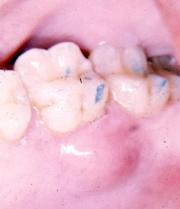

Il peut en être de même pour une poche parodontale.

Un contact glissant au cours de la fonction mandibulaire peut être à l'origine d'un abcès parodontal.